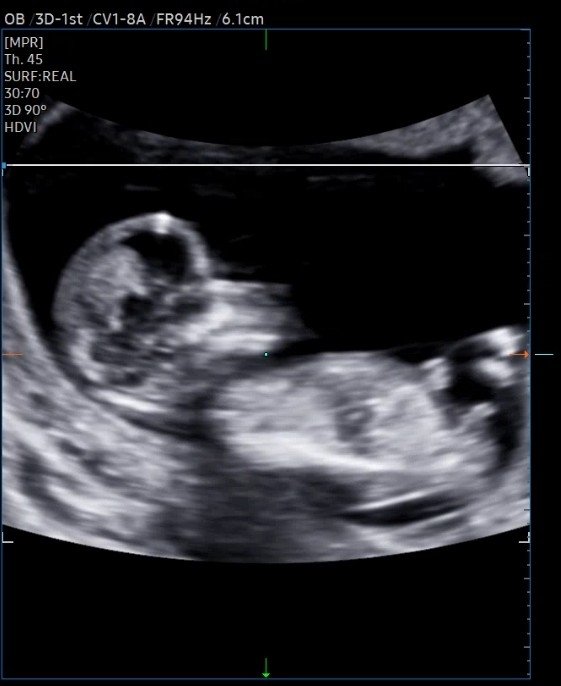

각도법 한번 봐주세요~~!!

16주에 성별나온다고했는데 너무너무 궁금해요!!ㅎㅎ

아들 같아요~